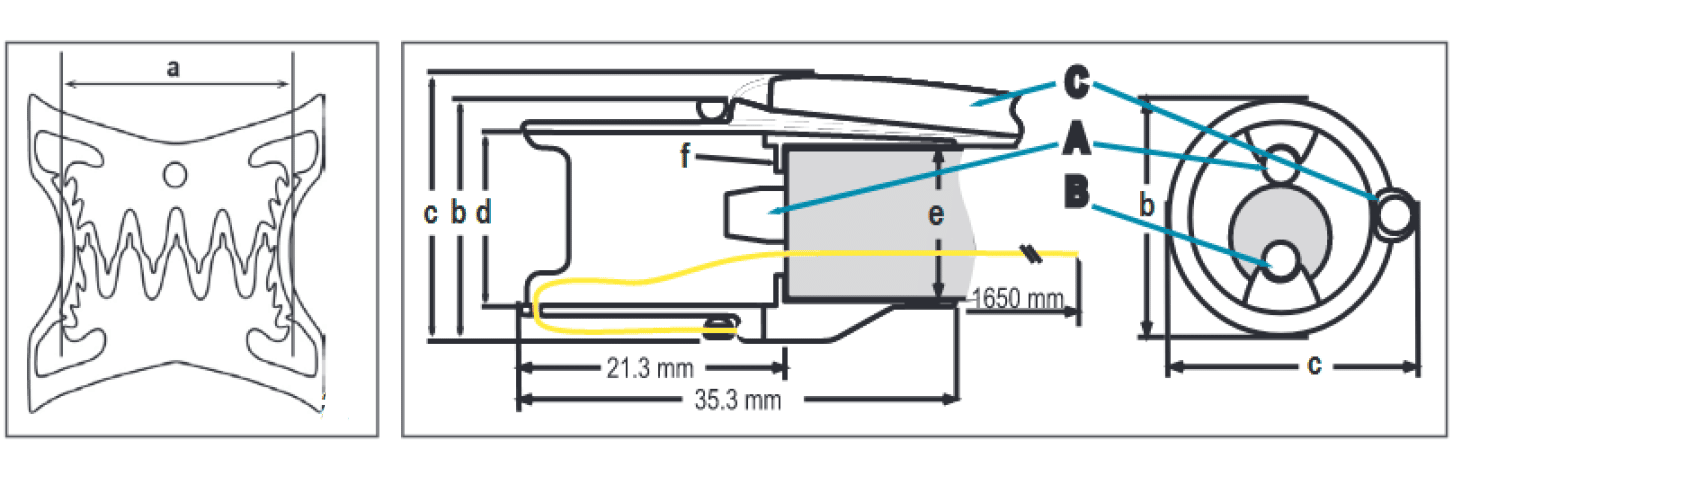

Das BARS®

BARS® besteht aus einer Applikationskappe mit darauf vormontiertem Clip und Faden, Fadenholer und BARS® Handrad.

Die BARS® Applikationskappe wird auf die Spitze des Endoskops montiert, während die Applikationshilfen in Arbeitskanälen außen am Endoskop entlanggeführt werden. Durch Drehen des Handrads wird der Faden gespannt und so der Clip ausgelöst.

Während der Clipapplikation verhindert der in die Anastomose eingeführte Ballon einen vollständigen Lumenverschluss und definiert das verbleibende Lumen.

Maße und Spezifikationen

| Kappenlänge | 35,3 mm |

| Clipbreite = Kompressionsbreite [a] | 12,4 mm |

| Min. Außendurchmesser [b] | 19,5 mm |

| Max. Außendurchmesser [c] | 21,2 mm |

| Innendurchmesser Kappe [d] | 13,1 mm |

| Kompatibel Endoskopdurchmesser [e] | 10,0–12,0 mm |

| Innerer BARS Arbeitskanal [A] | 3,0 mm Arbeitskanaldurchmesser | Max. 2,8 mm Instrumentendurchmesser |

| Endoskop-Arbeitskanal [B] | min. 3,7 mm |

| Äußerer BARS Arbeitskanal [C] | 2,8 mm Arbeitskanaldurchmesser | 2,6 mm Instrumentendurchmesser |

| Führungsdraht | 3700 mm Länge | 0,76 mm (0,03‘‘) Durchmesser |